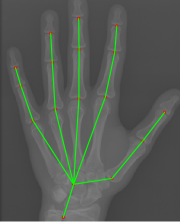

Refer to caption

Figure 1: (a) Original image. (b) Hand keypoint annotation used in BoNet [2]. (c) We convert the keypoints to bounding boxes which are used in our method to learn hand structure and extract local information.

We propose an anatomical local extraction module to learn the hand structure and extract local information for BAA. Unlike BoNet, our ALA-Net can extract the anatomical ROIs (Fig. 1) and evaluate the bone age jointly in an end-to-end manner. Benefiting from multi-task learning, the performances of anatomical region detection and BAA are significantly improved.

The original annotations of hand pose are a series of points, and we need to use boxes for local extraction. Hence, during the training time, we replace the point annotations by boxes centered at the points (Fig. 1). We use the same loss function as in [13] to train RPN, and we denote the loss function of RPN as LRPNsubscript𝐿𝑅𝑃𝑁L_{RPN}.